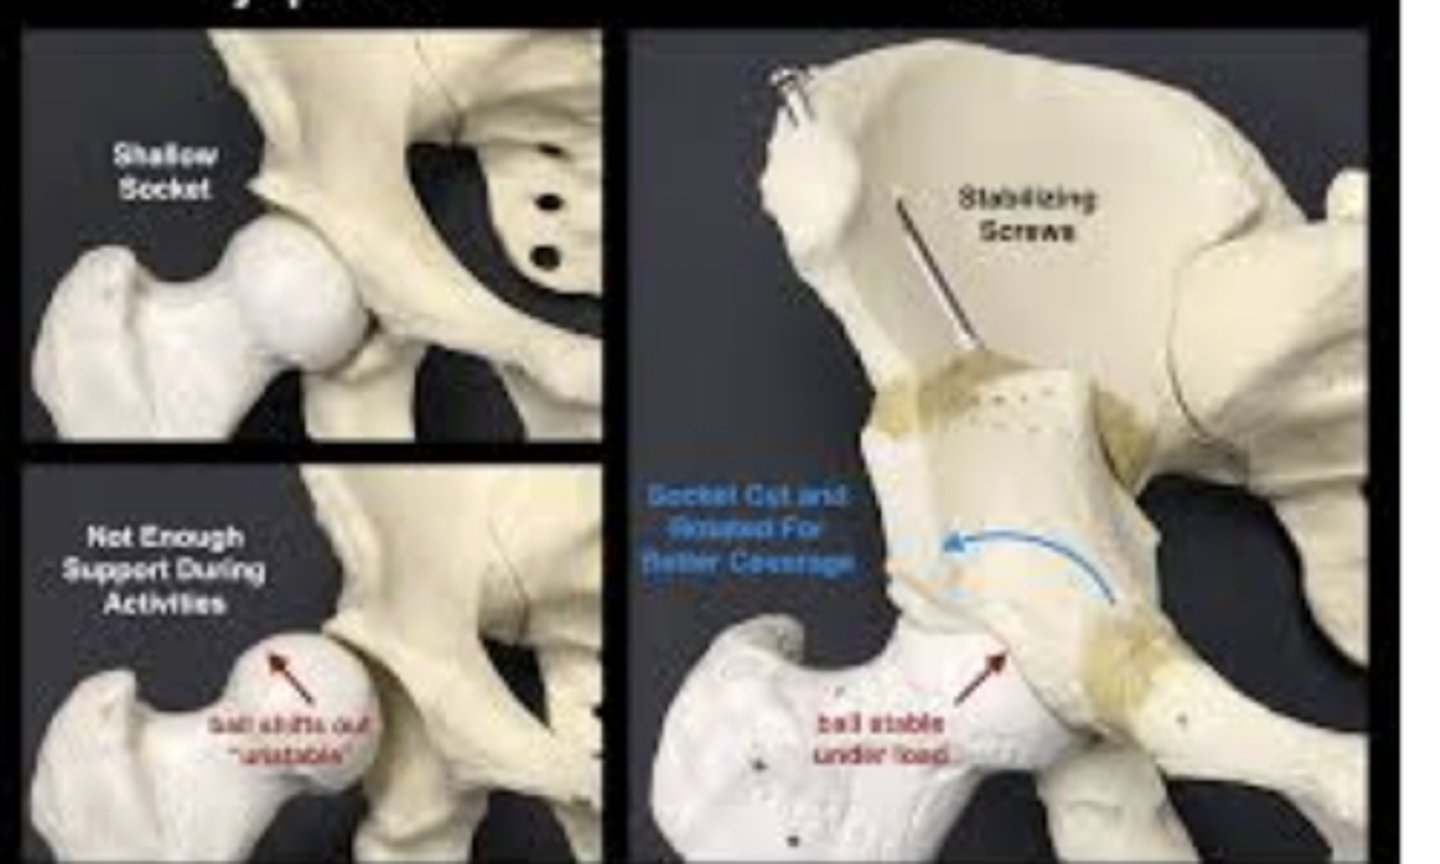

periacetabular osteotomy

used for hip dysplasia. break femur and pelvis, rotate them to provide greater joint angle